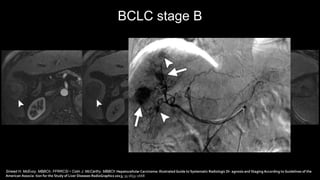

BCLC stage B

Sinead H. McEvoy, MBBCh, FFRRCSI • Colin J. McCarthy, MBBCh Hepatocellular Carcinoma: Illustrated Guide to Systematic Radiologic Di- agnosis and Staging According to Guidelines of the

American Associa- tion for the Study of Liver Diseases RadioGraphics 2013; 33:1653–1668